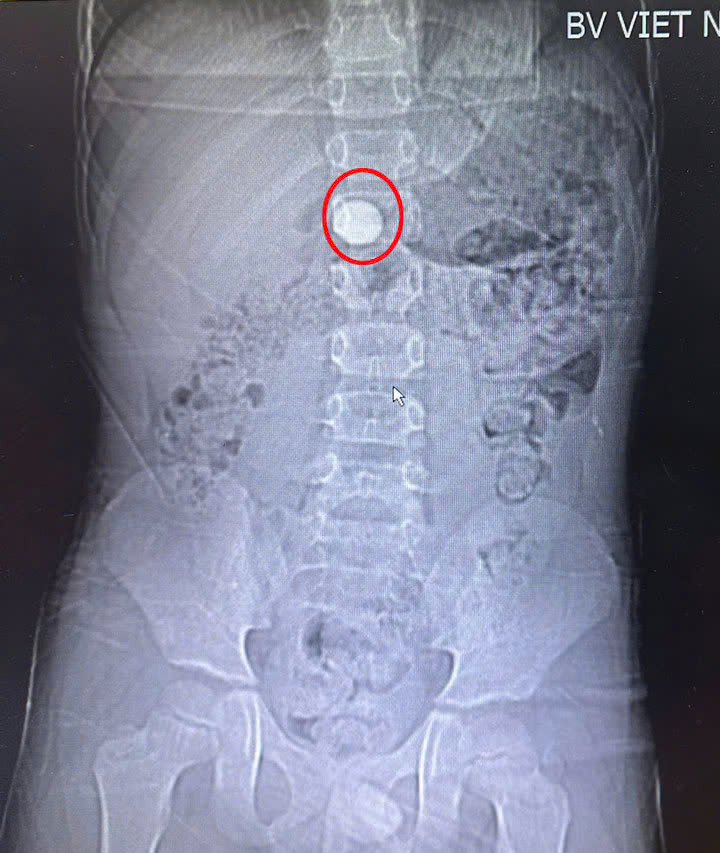

Tại bệnh viện, trên hình ảnh CT.Scanner ổ bụng cho thấy dị vật dạng hình tròn trong hang vị dạ dày. Bệnh nhi được chỉ định và tiến hành nội soi gây mê để gắp dị vật đường tiêu hóa. Dị vật được gắp ra là một viên bi tròn thủy tinh màu xanh, đường kính 15mm. Hiện sức khỏe trẻ ổn định và đã được xuất viện.

| Hình ảnh dị vật trong dạ dày của bệnh nhi - Ảnh BVCC |